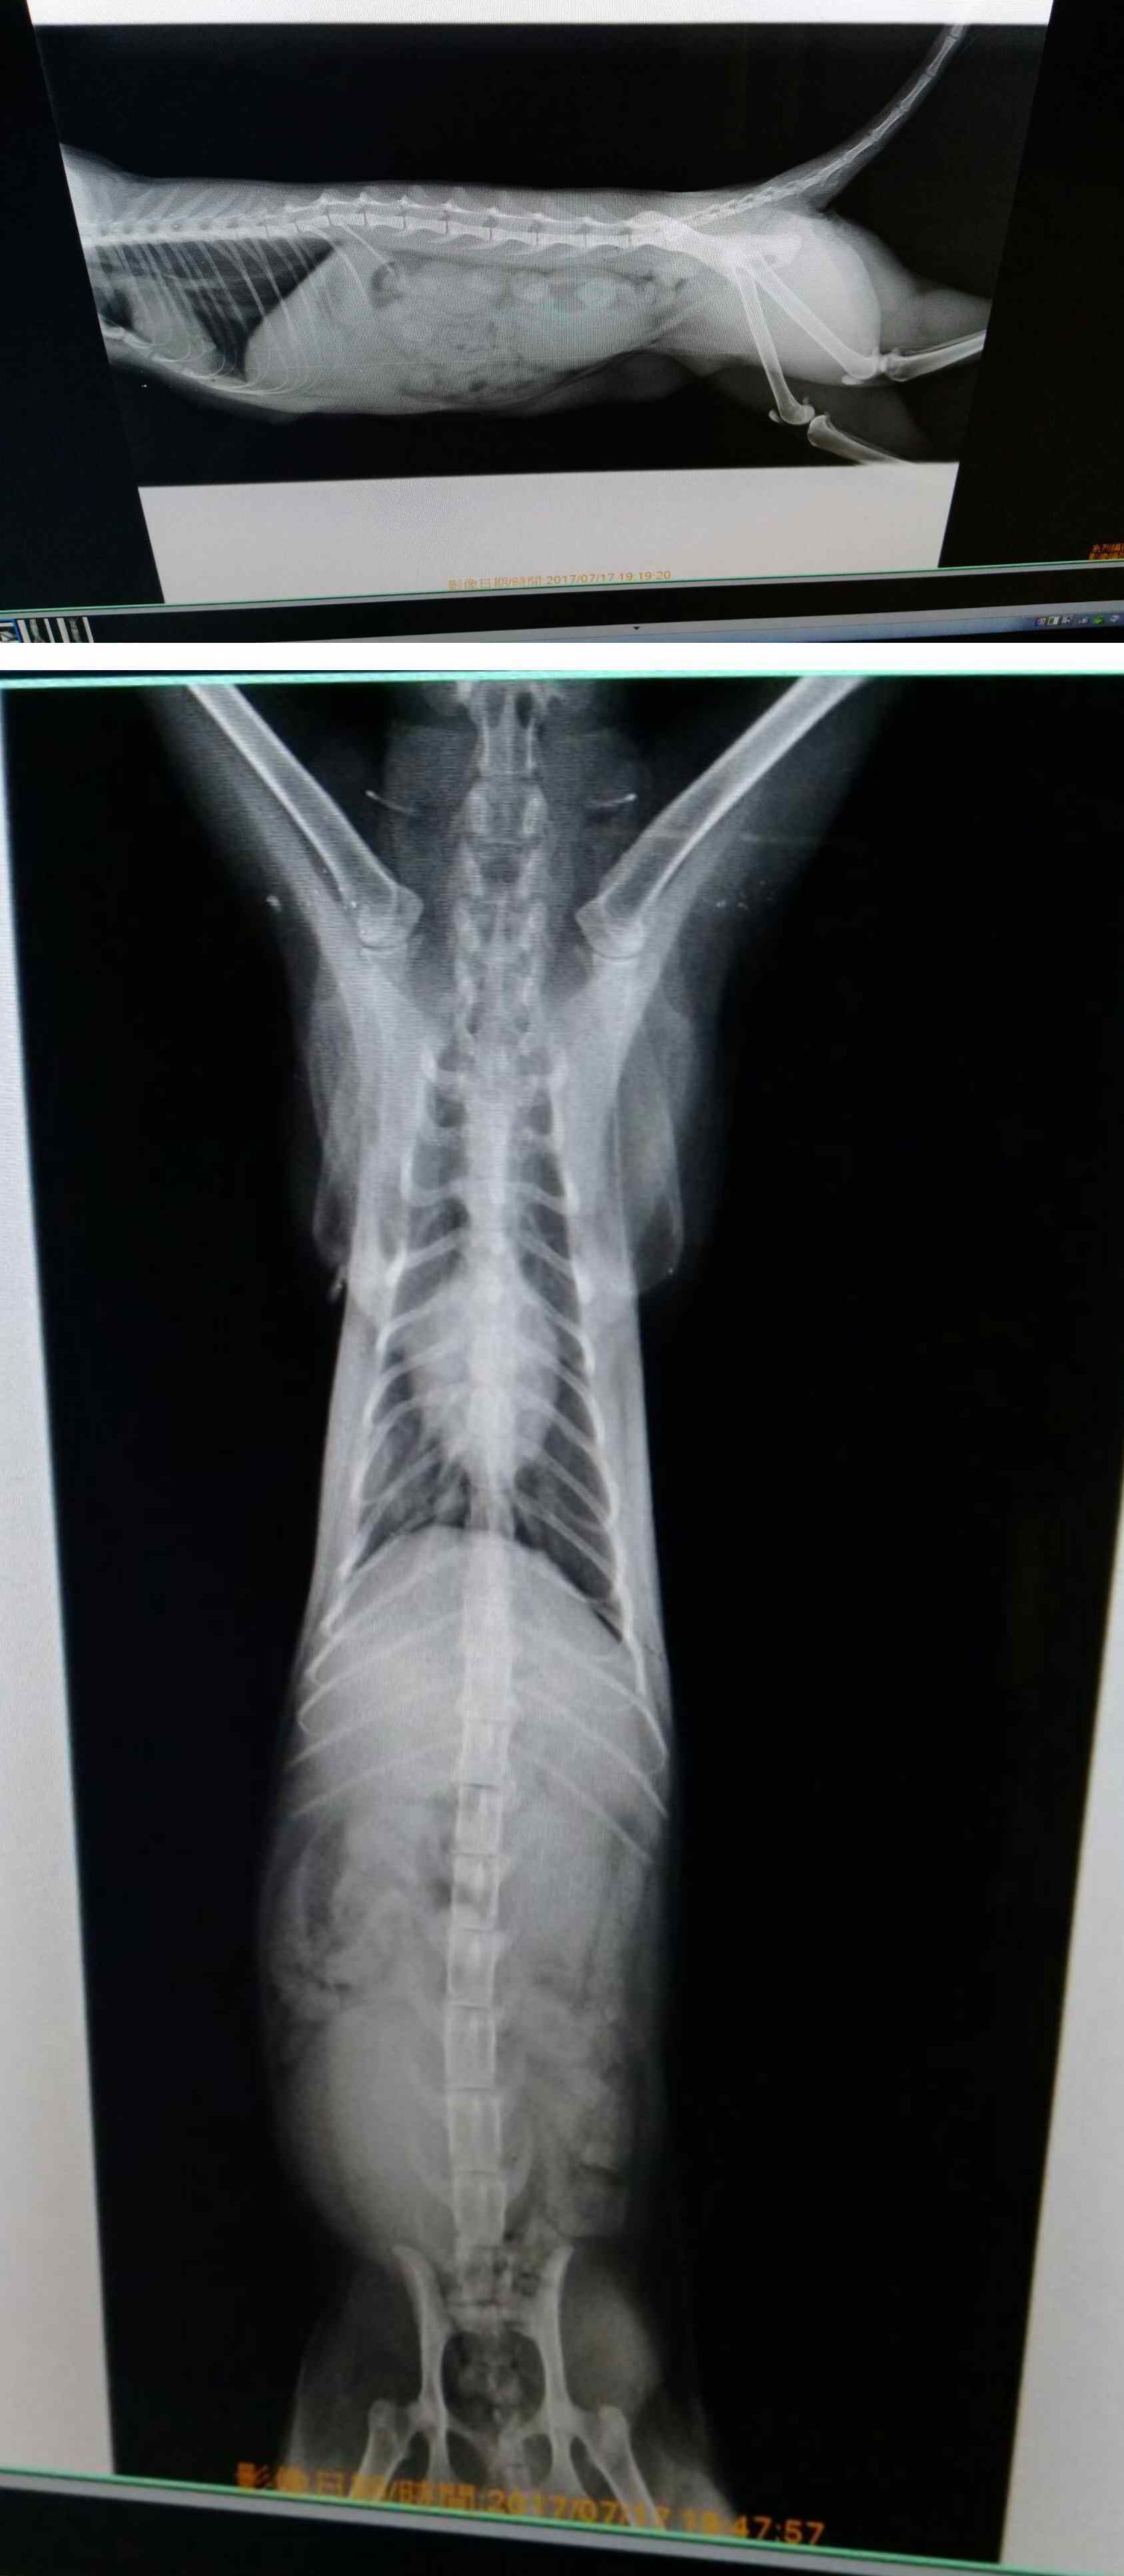

醫生評估貓咪的傷勢,除外傷外,還有氣胸,脊椎錯位等現象。

請醫生先給予治療後才詢問了預估價格,回家後反覆的掙扎,想到脊椎的問題,後續會有長時間回診及復健等開銷,實在沒辦法,故厚著臉皮望協會能給予醫助的幫忙。

7月18日進行了氣胸和傷口縫合,手術很順利完成。之後長達一個月的時間靠人工擠尿擠便,不過食慾很好,這段時間中,也慢慢的會親人了,很會撒繳,換藥、敷藥、餵藥、或復健,任何的醫療行為都乖乖不反抗,格外令人心疼。

期間復健的成果讓她可以慢慢的站著,也可以自己排便排尿,令人欣慰。

感謝德民醫院所有醫生和醫護助理,貓咪除了無法行走,但狀況一切恢復良好,食慾也很好,所以評估復原狀況後,在8月23日進行了節育手術。